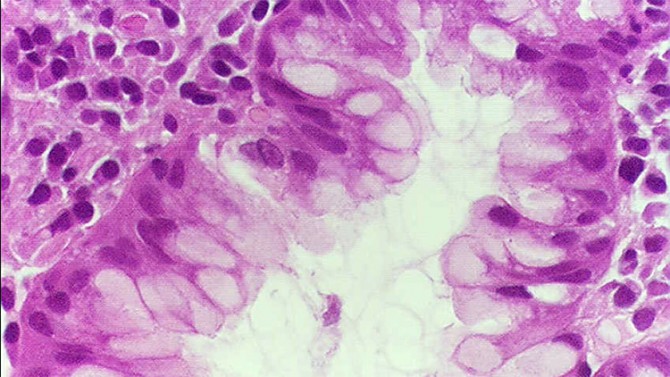

Científicos advierten que una nueva ‘superbacteria’ que podría acabar con la humanidad ya ha llegado a Europa. Registrada por primera vez en China el mes pasado, es inmune a los antibióticos más potentes.

Científicos advierten que una nueva ‘superbacteria’ que podría acabar con la humanidad ya ha llegado a Europa. Registrada por primera vez en China el mes pasado, es inmune a los antibióticos más potentes.

La ‘superbacteria’ resistente a todos los métodos de tratamiento existentes llegó a Europa a través de la carne de pollo y causa una fuerte neumonía imposible de curar, informa el diario ‘The Sun’.

El primer caso ha sido registrado en Dinamarca, donde recientemente han hospitalizado a un paciente. Los análisis han revelado que la bacteria que afectó al ciudadano danés es una nueva versión mortífera de las bacterias del tipo ‘Escherichia coli’, que contienen un gen mutado conocido como MCR-1 y es resistente a los antibióticos más potentes, incluso a la colistina.